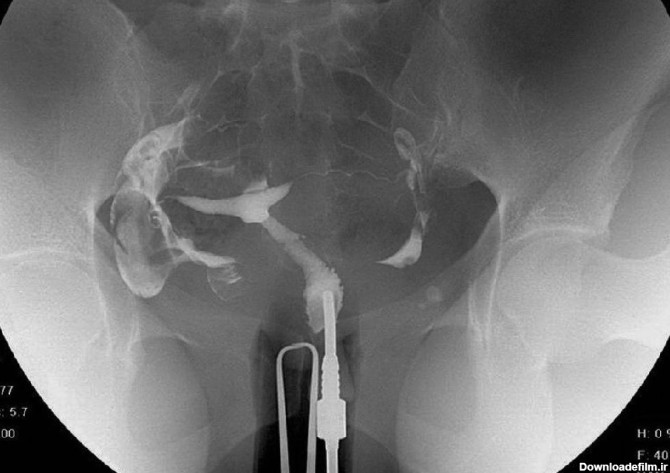

از مزایای عکس رنگی رحم غیرتهاجمی بودن آن است. پزشک میتواند با گرفتن عکس رنگی رحم اطلاعات مفیدی درباره ناهنجاریهای رحمی بدست آورد. در این مق